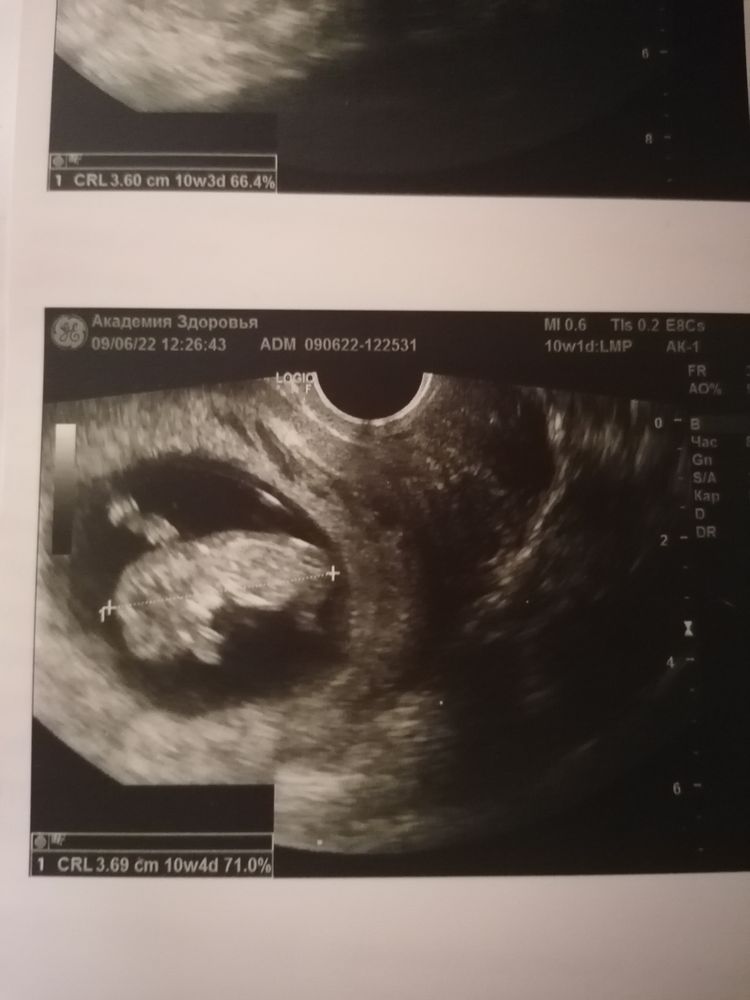

Узи 10 недель 1 день

09.06.2022